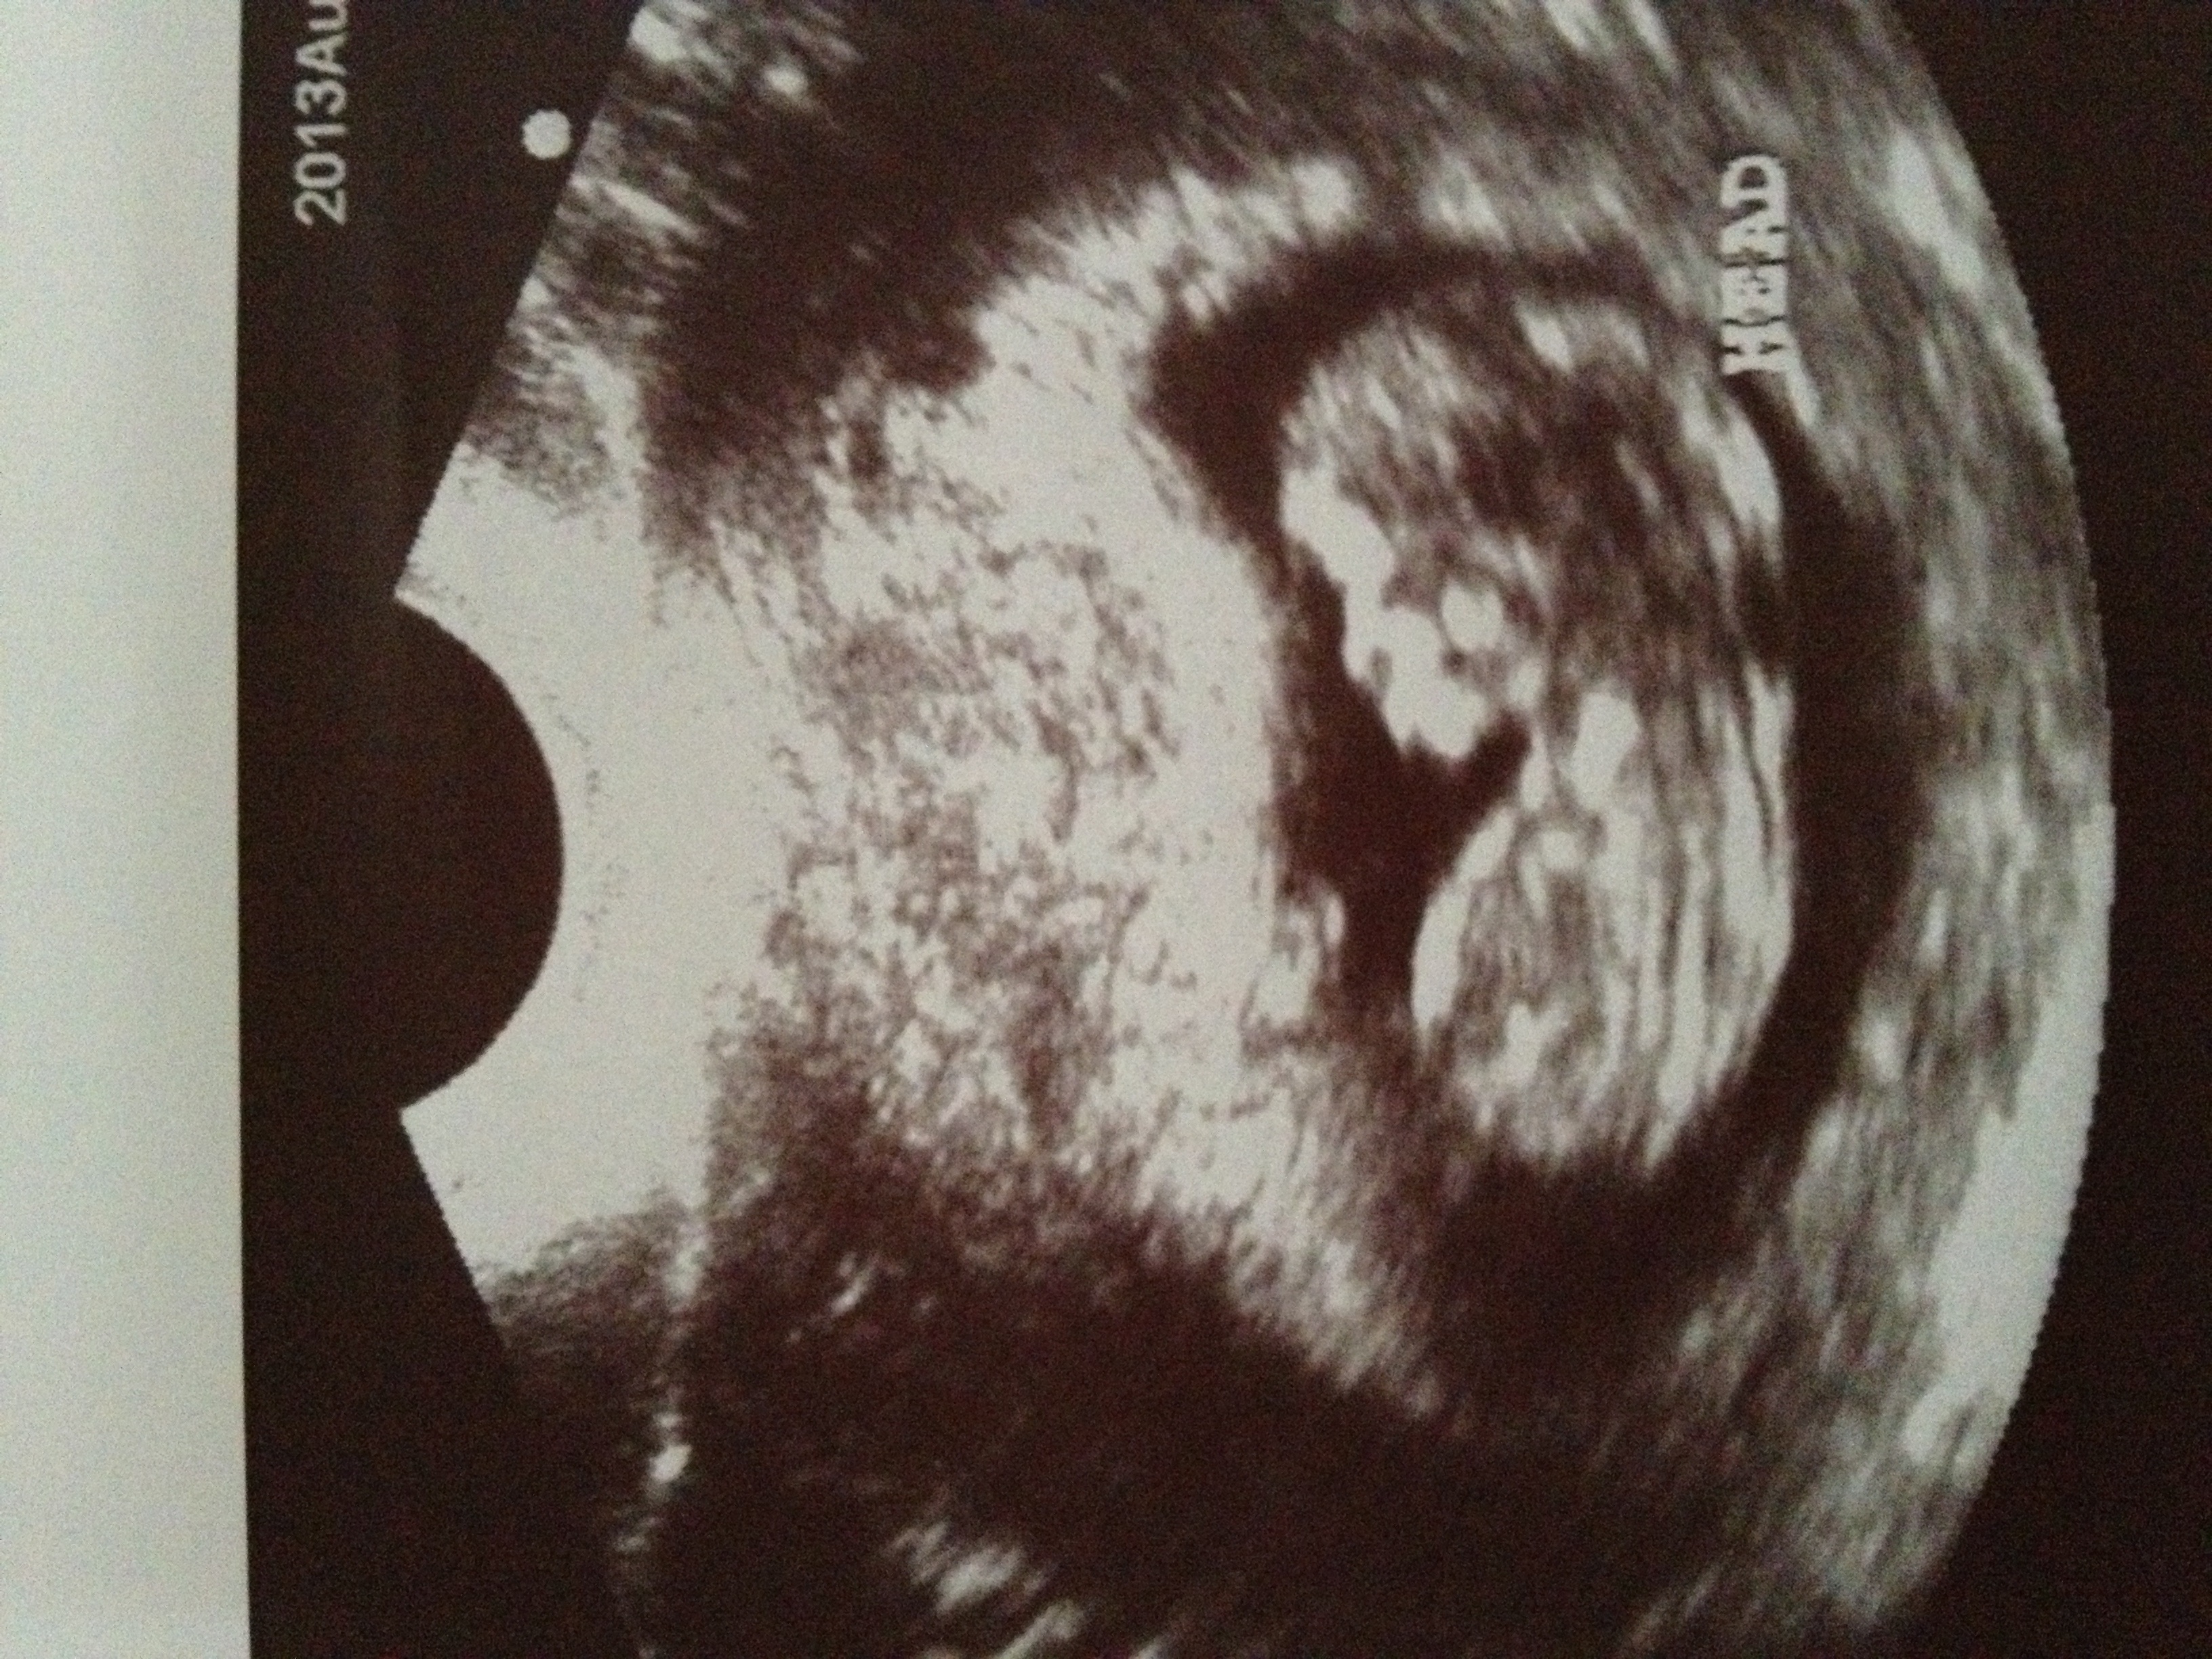

I had my OB appt and saw my little one again. I am 11 weeks. Last time I saw him/her it looked like a kidney bean dot.

Today I heard the heartbeat and got this pic!!!